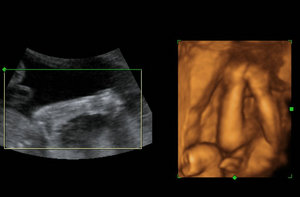

其次,检查功能更强大且更加精准的胎儿产前排畸及缺陷儿终极诊断。因为可以在很短的时间之内,更加精准的来诊断宫内胎儿的生长发育情况,不仅可以排查胎儿的体表出现的问题,如唇裂、脊柱裂与骨骼发育不良等畸形,更能为早期诊断胎儿先天性心脏疾病和体表疾病提供准确的科学依据。

再次,它还可以拍摄极为细致的立体与连动的影像,让准爸妈们亲眼看见胎儿的实时动态图像,能够立体的显示出胎儿表面器官的发育情况,这样以利于判断胎儿情况并及时发现是否存在异常。

温馨提示,四维彩超是目前世界上较为先进的彩色超声设备.因为它提供了包括腹部、血管、小器官、产科、妇科、泌尿科及新生儿和儿科等多领域的多方面的应用。